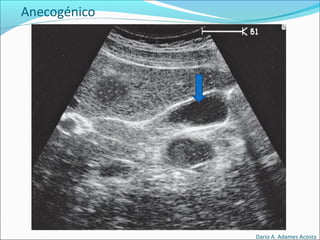

Patrones Ecográficos

Escala de grises

Depende de la densidad de los elementos y capacidad

para producir Ecos.

Anecogénico

El elemento objetivado es negro

Anecogénico

• #42 Que tanto eco produce una estructura/elemento con respecto al resto de los elementos. IMÁGENES ELEMENTALES IMÁGENES ANECOICAS Se producen cuando el haz de ultrasonido atraviesa un medio sin interfases reflectantes en su interior. Suelen ser de este tipo las Lesiones Ocupantes de Espacio (LOES), totalmente líquidas como los quistes, que además tienen el Artefacto denominado Refuerzo Acústico Posterior y algunas LOES sólidas pero de estructura histopatológica muy celular como en las neoplasias hematológicas, en especial los linfomas y en este caso no suelen tener Refuerzo Acústico Posterior. IMÁGENES HIPOECOICAS Se producen cuando en el interior de la estructura anormal existen interfases de menor ecogenicidad o en menor número que en la estructura normal que la circunda. 21/09/2010 ecografia generalidades medspain.com/…/leccion_03_eco.htm 1/3 Suele ser de este tipo las LOES correspondientes a tumores muy celulares, con poca fibrosis y sin estructuras glandulares muy desarrolladas y con vasos de paredes finas. IMÁGENES HIPERECOICAS Se producen cuando en el interior de esa estructura existen interfases muy ecogénicas o en mucho mayor número que en el parénquima normal que la circunda. Son de este tipo las ocupaciones tumorales que tiene estructuras glandulares desarrolladas en su interior, que tienen vasos de paredes gruesas y estructura tortuosa o que tiene gruesos septos fibrosos.